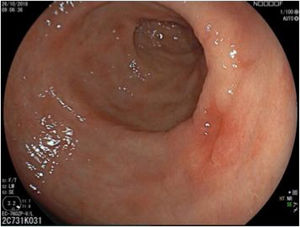

The endoscopic classification utilized to diagnose all lesions included in the present study was the Paris classification, whose validity is widely accepted by the different international consensuses and clinical guidelines. The following techniques were employed in the present study for the detection and characterization of the gastric lesions as follows: High-resolution white light endoscopy associated with a detailed and systematic review of the integrity of the gastric mucosa was initially utilized to identify lesions (Fig. 1). FICE (Flexible Spectral Imaging Colour Enhancement, Fujifilm Co., Japan) virtual chromoendoscopy or chromoendoscopy with 0.4% indigo carmine contrast staining were then employed to better characterize and delimit the lesions found (Fig. 2). In some cases, to optimize the evaluation of gastric abnormalities found (emphasizing special details, such as determining the microvascular pattern and specific alterations of the microsurface of the mucosa), minimum endoscopic image magnification, together with LCI (Linked Color Imaging, Fujifilm Co., Japan) and BLI (Blue Laser Imaging, Fujifilm Co., Japan) virtual chromoendoscopy, was utilized to show the demarcation line of the neoplastic lesion (Fig. 3), as well as microvascularization alterations (Fig. 4).